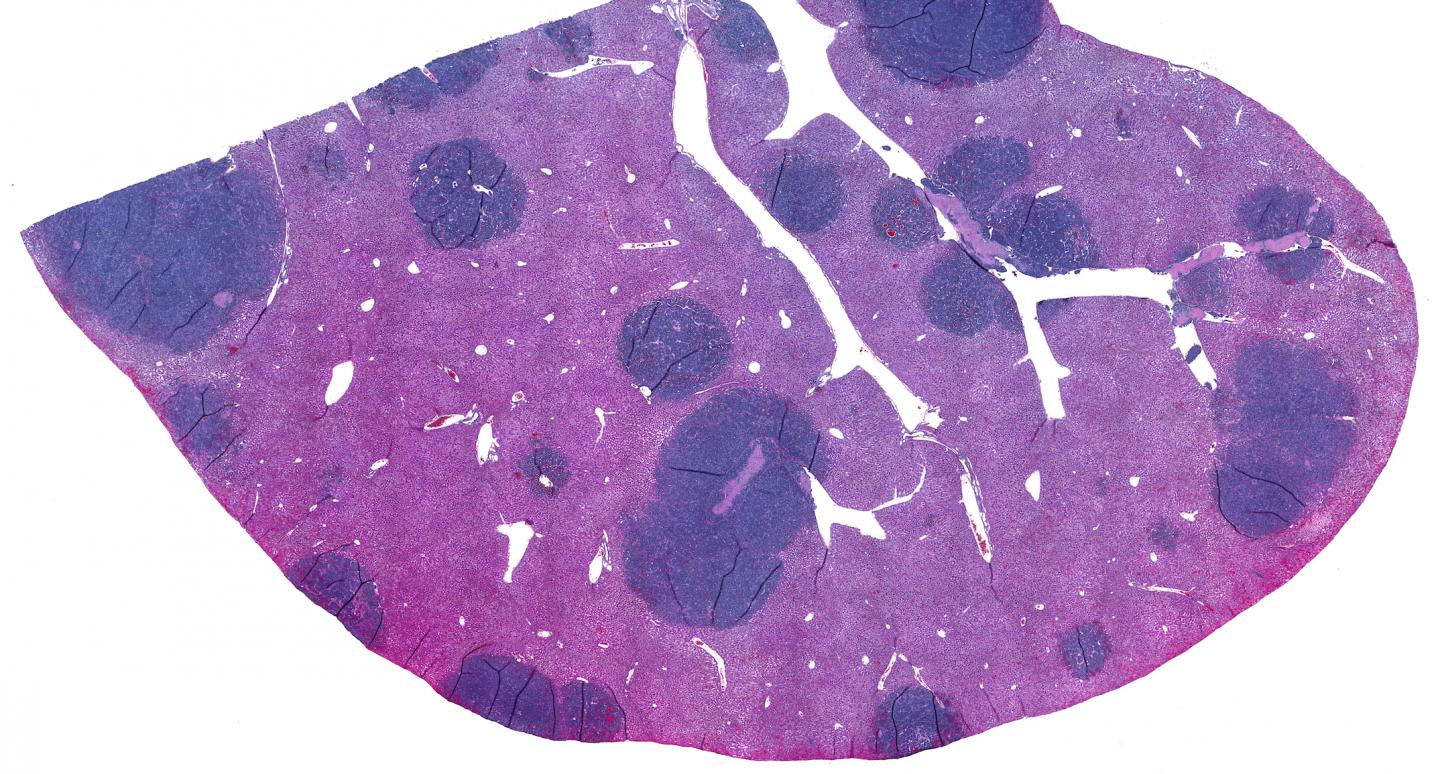

Small cell lung cancer (SCLC) is a highly metastatic cancer. The liver is one of the common sites of metastases, as seen in this image of mouse liver with metastatic SCLC lesions. SCLC tumors are composed of tightly packed epithelial cells with few immune cells infiltrating inside the tumor.